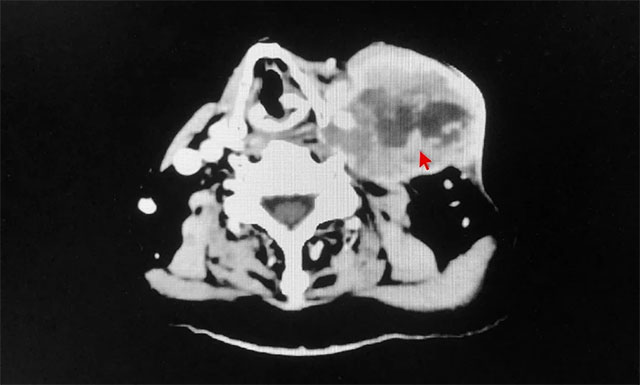

近日,上海蓝十字脑科医院肿瘤科(放疗)收治了一位喉癌淋巴转移患者。年过七旬的患者李某(化名),因“喉癌术后8年,左侧颈部包块2月余”入院。该患者于2013年在福建某大医院确诊喉部占位,伴喉白斑,并行喉部肿瘤微创切除术,术后病理显示:原位癌。其后,患者喉部肿瘤两次复发,行手术切除治疗。去年10月,患者发现左侧颈部有淋巴结肿大,进行性增大。于今年2月行左颈部淋巴结转移灶穿刺活检,病理示:鳞状细胞癌,中度分化。

▲ 患者左侧颈部淋巴结转移,肿瘤体积较大

经亲友推荐,患者慕名来到上海蓝十字脑科医院寻求进一步治疗。经详细检查,该患者喉癌病史数年,诊断明确,既往已行三次手术,目前左侧颈部淋巴结转移,肿瘤体积较大,且肿瘤包绕血管,无再次手术适应症。医院肿瘤科(放疗)主任王晓东与其团队就患者病情予以详细讨论及评估,结合患者入院后各项常规检查结果,排除放射治疗禁忌症,明确告知患者及家属目前病情情况、放射过程中各种临床并发症及副作用,以及患者整体预后情况,予以签字同意后,王晓东团队仔细勾画患者肿瘤靶区及临床靶区,物理师精心设计放射治疗方案,为患者开展了加速器放射治疗。